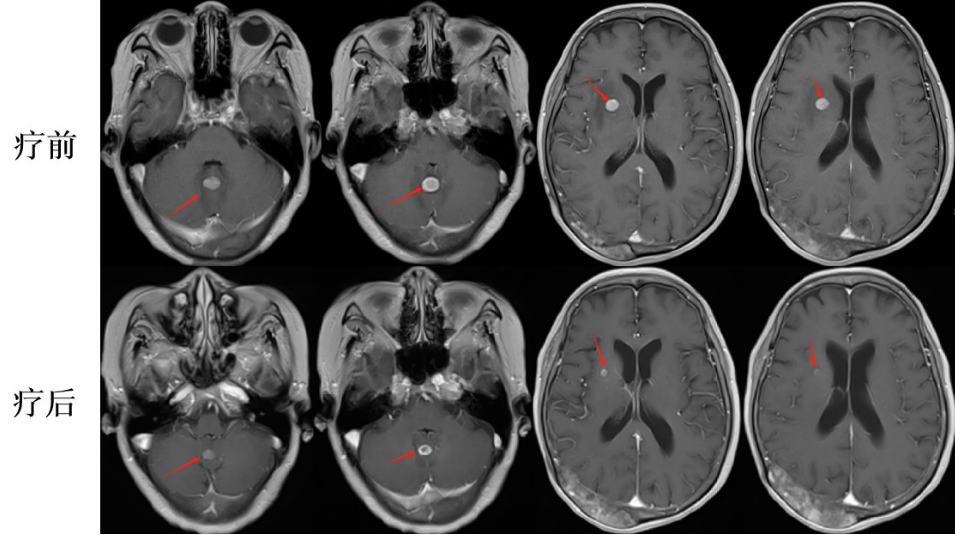

張老太,70歲, 2024年8月因頭暈頭痛,頻繁嘔吐等癥狀入院。頭部磁共振檢查顯示,顱內(nèi)多發(fā)腦轉(zhuǎn)移瘤病灶(見圖)。同時(shí),患者胸部CT檢查可見肺內(nèi)多發(fā)較大腫瘤病灶(見圖)?;颊哂?024年8月20日行CT引導(dǎo)肺腫物穿刺活檢。病理診斷為肺腺癌。綜合診斷為肺腺癌IVB期,腦、肺內(nèi)、右腎上腺多發(fā)轉(zhuǎn)移?;颊哌M(jìn)一步行腫瘤組織基因檢測(cè)和免疫檢查點(diǎn)分子——細(xì)胞程序性死亡配體1(PDL1)檢測(cè)。

圖注:磁共振檢查,小腦蚓部、右側(cè)基底節(jié)-放射冠異常信號(hào)影,考慮轉(zhuǎn)移瘤,伴灶周水腫。

患者于2024年08月20開始接受頭部放療。采用最新一代智慧化精準(zhǔn)放療系統(tǒng)——Halcyon“速銳刀”,成功控制患者全部顱內(nèi)病灶,過程順利,沒有明顯副反應(yīng)發(fā)生。患者基因檢測(cè)結(jié)果為陰性,沒有找到具有靶向治療藥物的突變基因。此外,患者年齡較大,體質(zhì)較弱,全身多發(fā)轉(zhuǎn)移病灶,為治療帶來了巨大的挑戰(zhàn)。然而,患者PDL1檢測(cè)顯示,PDL1高表達(dá)(PD-L1 TPS=98%),提示免疫治療有效率較高。潘振宇教授團(tuán)隊(duì)為患者制定了個(gè)體化精準(zhǔn)腫瘤治療方案,僅僅每3周應(yīng)用1次免疫治療藥物。經(jīng)過3次治療后復(fù)查,患者肺內(nèi)病灶顯著縮退,顱內(nèi)病灶縮退。治療過程中,僅出現(xiàn)一過性皮疹。目前患者恢復(fù)良好,生活完全自理。

圖注:治療后復(fù)查磁共振顯示,顱內(nèi)病灶明顯縮小。